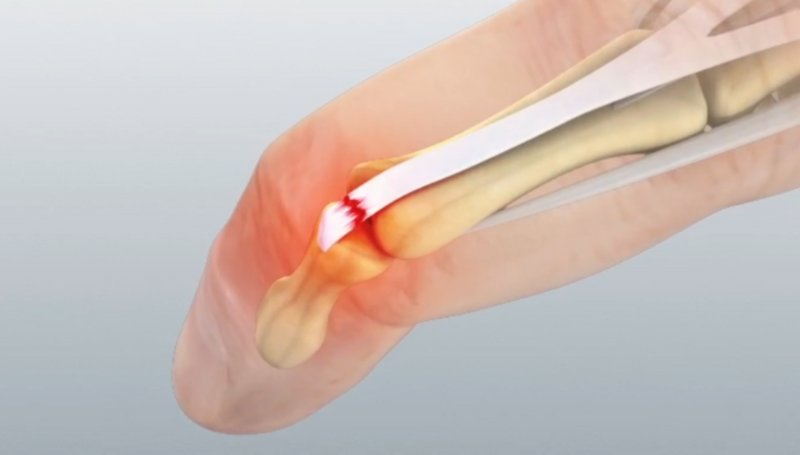

Poškodbe rok sodijo med najpogostejše poškodbe. Odprte poškodbe, kjer je prisotna rana na koži so nevarnejše od zaprtih, saj je rana vstopno mesto za bakterije, ki lahko povzročijo vnetje. Pri vreznih in vbodnih ranah, velikost rane na koži običajno ni sorazmerna s poškodbo globje ležečih struktur. Zmečkanine in raztrganine nastanejo zaradi delovanja večjih sil in pogosto so prisotne vrzeli tkiv, ki jih je potrebno nadomestiti. Amputacija pomeni, da je del telesa v celoti ločen od amputacijskega krna.